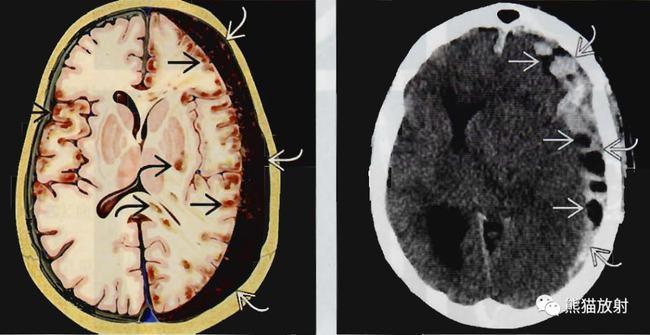

临床医学 如何分析脑ct(同济大学)ppt 硬膜下血肿 上图:急性期 左图

硬膜外血肿与急性硬膜下血肿在ct上的区别

急诊头部ct扫描显示,右侧急性硬膜下血肿,脑挫伤和蛛网膜下腔出血